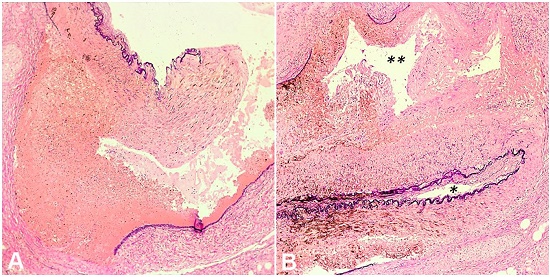

The postmortem period was 24 hours. On external examination, the skin was pale and elastic. There were widened atrophic scars in the left paratracheal and supraclavicular regions from prior surgical procedures. There were no apparent deformities of the axial or appendicular skeleton. On internal examination, there were bilateral serous pleural effusions (right, 150 mL; left, 50 mL). The visceral pleura exhibited numerous fibrous adhesions to the chest wall and pericardium, bilaterally. The pericardial sac was dry. There was hemoperitoneum, 900 mL of blood and 910 mL of clots. Fibrous and fibrinous adhesions between loops of small intestine and abdominal wall were present in the lower abdominal cavity associated with a 5-cm area of serosal purulent exudate. There was a perforation of the small intestine (Figure 1).

The remainder of the small and large intestines exhibited thin and translucent walls with loss of mucosal folds and reduced circumference. An area of fresh soft tissue hemorrhage tracked down to the gallbladder neck and hepatic hilum. Careful dissection and microscopic examination of the gallbladder neck revealed rupture and dissection of the cystic artery (Figure 2, 3 and 4).